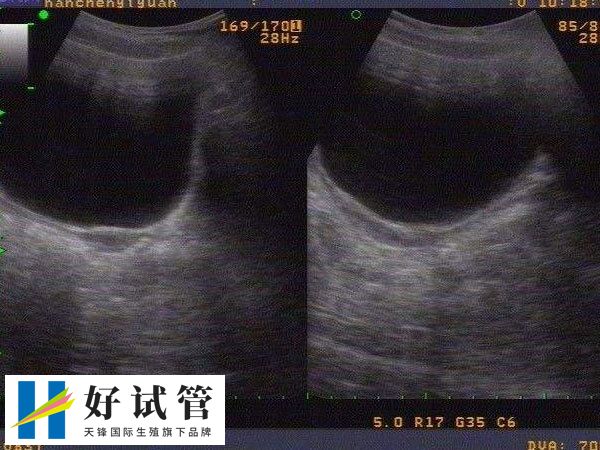

纵隔子宫能不能做试管婴儿

一般来说,纵隔子宫的女性可以进行试管婴儿,但需要先进行手术治疗以纠正子宫纵隔的情况。毕竟纵隔子宫可能导致子宫腔形态异常,增加流产和早产的风险。为了确保试管妊娠的安全和成功率,通常建议患者在进行任何医疗决策前,建议咨询专业的生殖医学专家,进行全面的身体检查和评估。